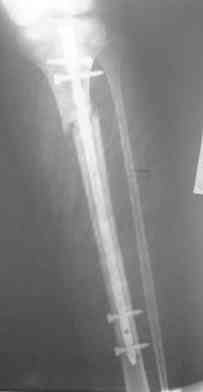

Re: Интрамедуллярный остеосинтез. Как избежать смещение?

Савранский Александр 30 Декабрь 2006, 02:06

Оставить как есть,но с нагрузками не торопиться,на будущее-нет ЭОП,есть рентген-интраоперационный.

да какие последствия, разве боль, косметический дефект, на гвозде и так срастетсЯ, а какие требования? если высокие- коррекция оси в АВФ, после удаления гвоздя, затем ORIF доступными имплантами (если нет ЭОПа).С Н.Г.

не трогайте ничего ! срастется . Единственно стоит проверить соответствие осей г\ст и к\с (чтобы не было ротации !!!)

конечно в данном случае все хорошо срастется.На будущее при таких высоких переломах,хорошо помогают направляющие винты.Они вводятся спереди назад(до введения стержня) для предотвращения бокового смещения или снуружи ввнутрь ,для предотвращения передне - заднего.Они не дают стержню сместить перелом.ЭОП не нужен,обычный рентген о опер.достаточен.

Удобнее для этих целей использовать спицы. Их и быстрее/легче ввести, и в случае слишком агрессивного введения они гнутся и удается провести гвоздь, в то время как с винтом он заклинится или расколется кость.